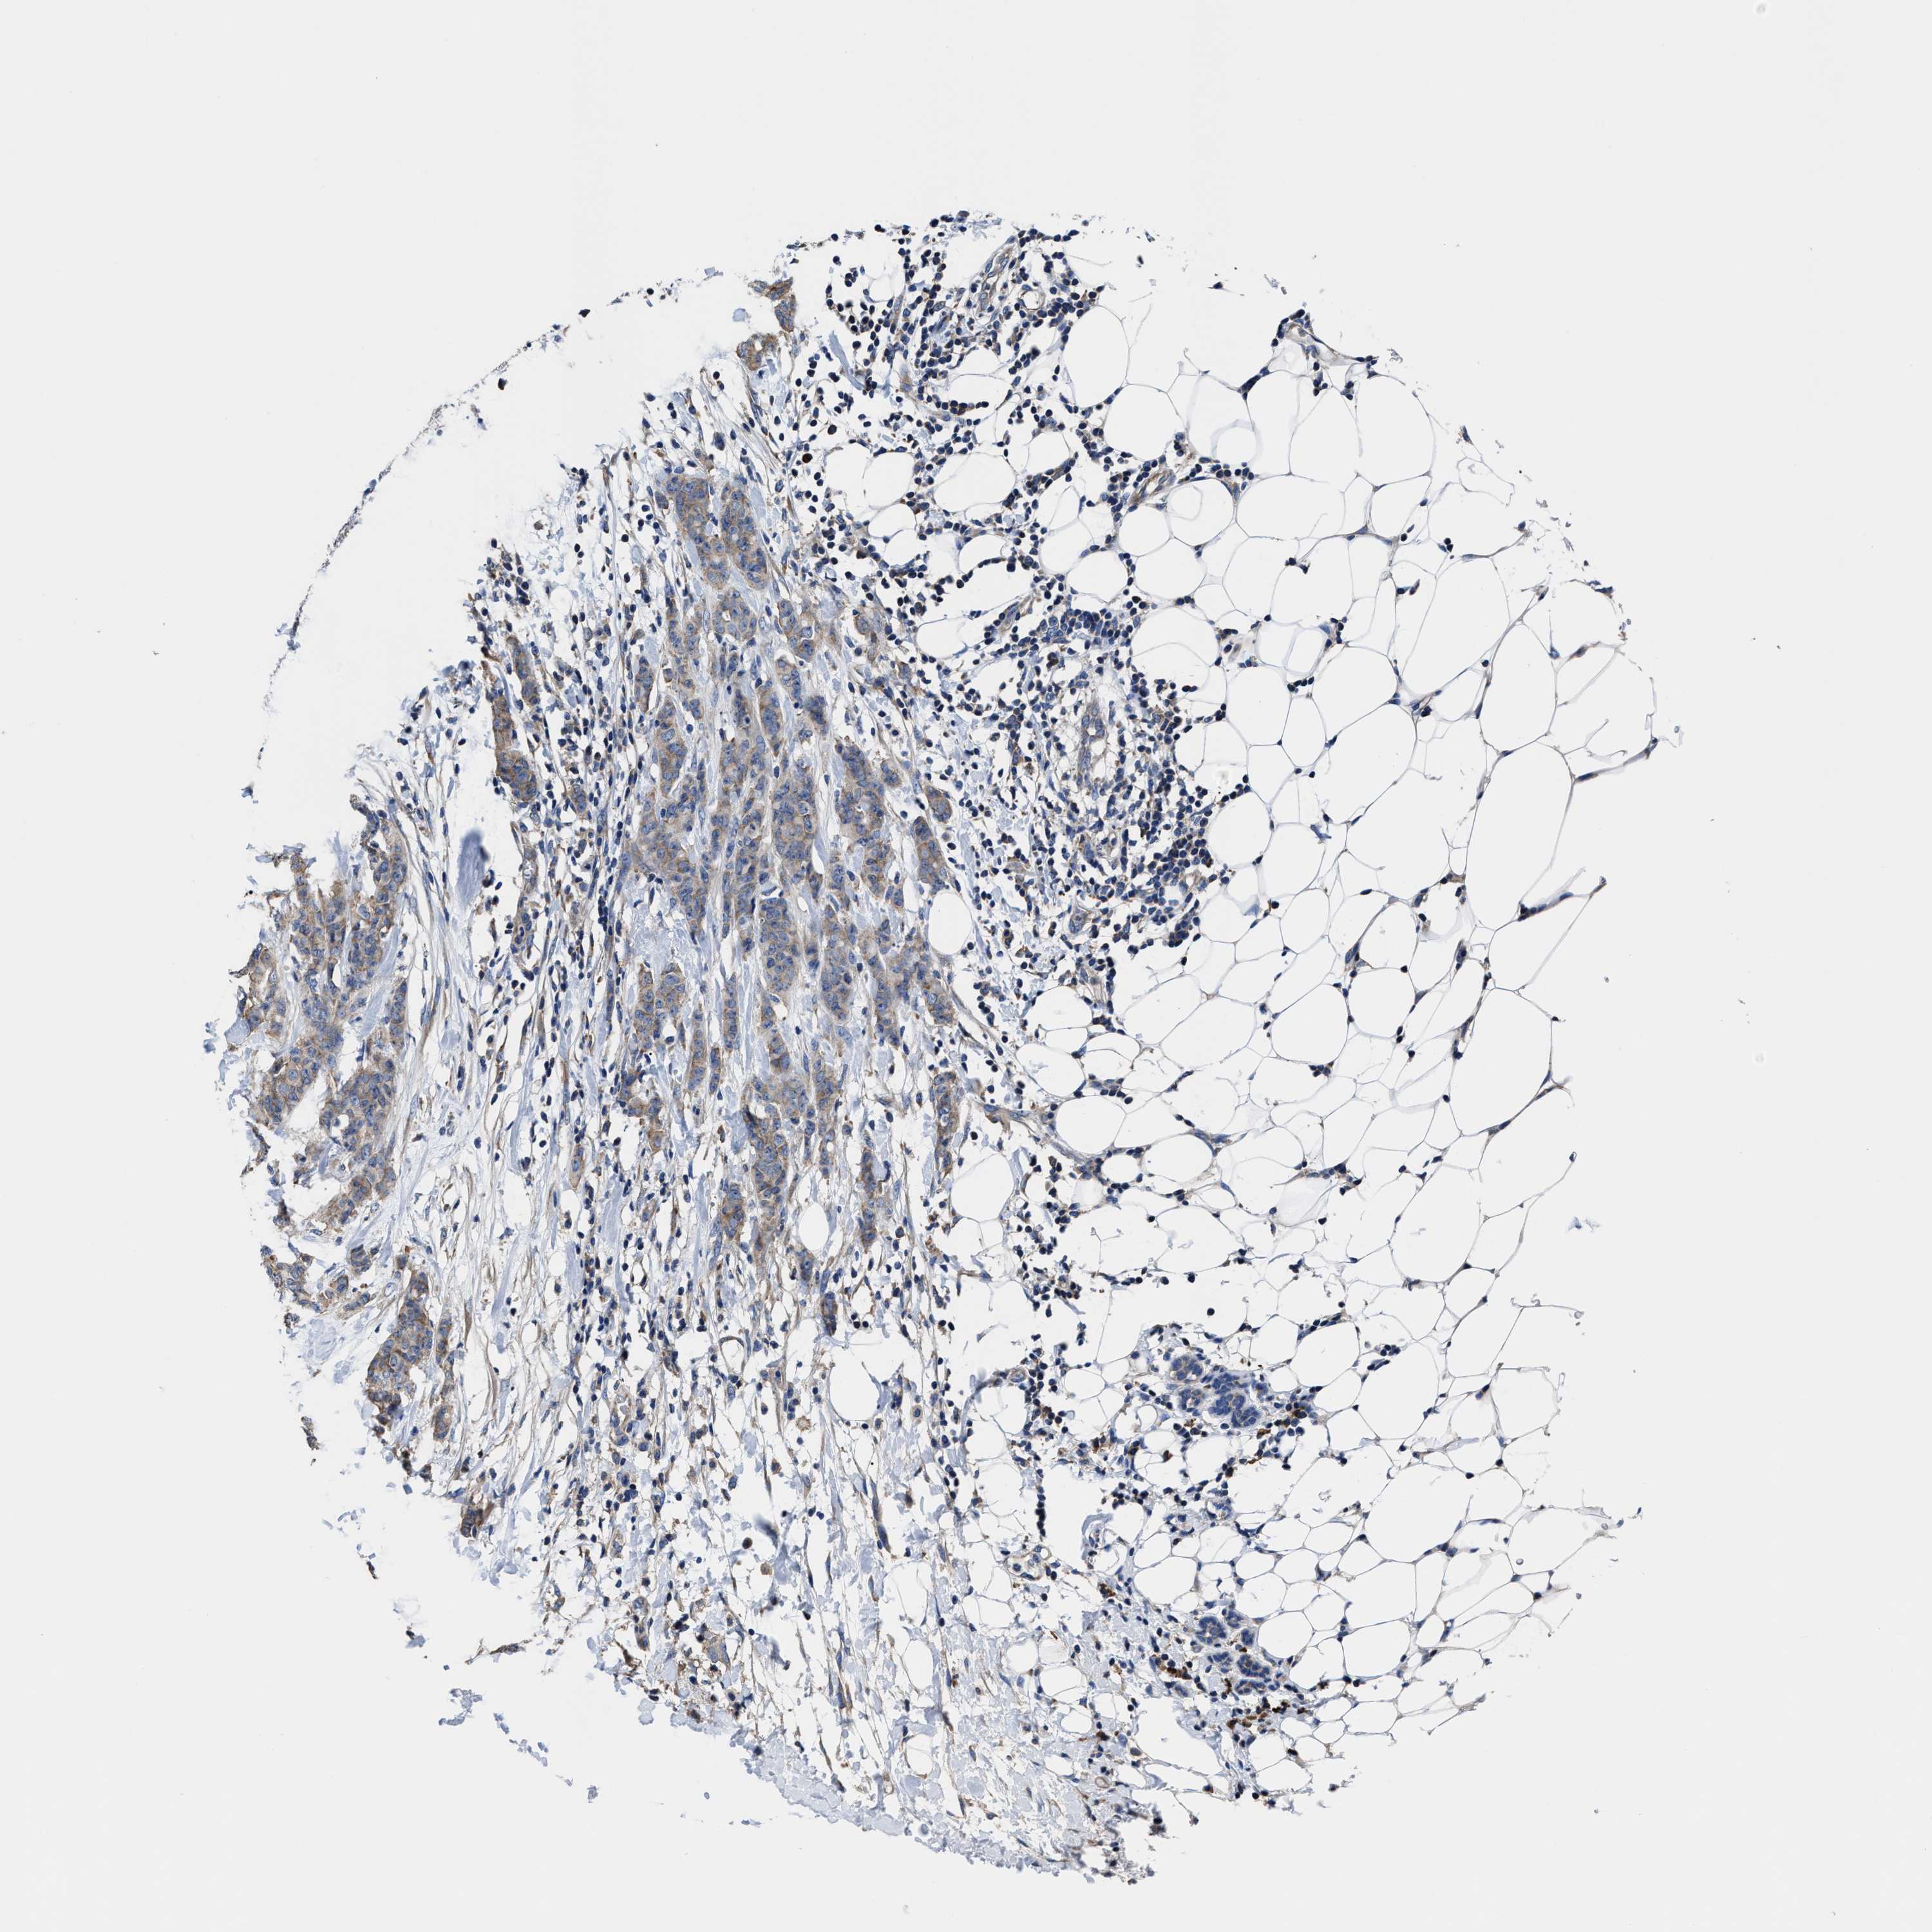

BRCA TCGA BRCA VALIDATION PROTEIN EXPRESSION